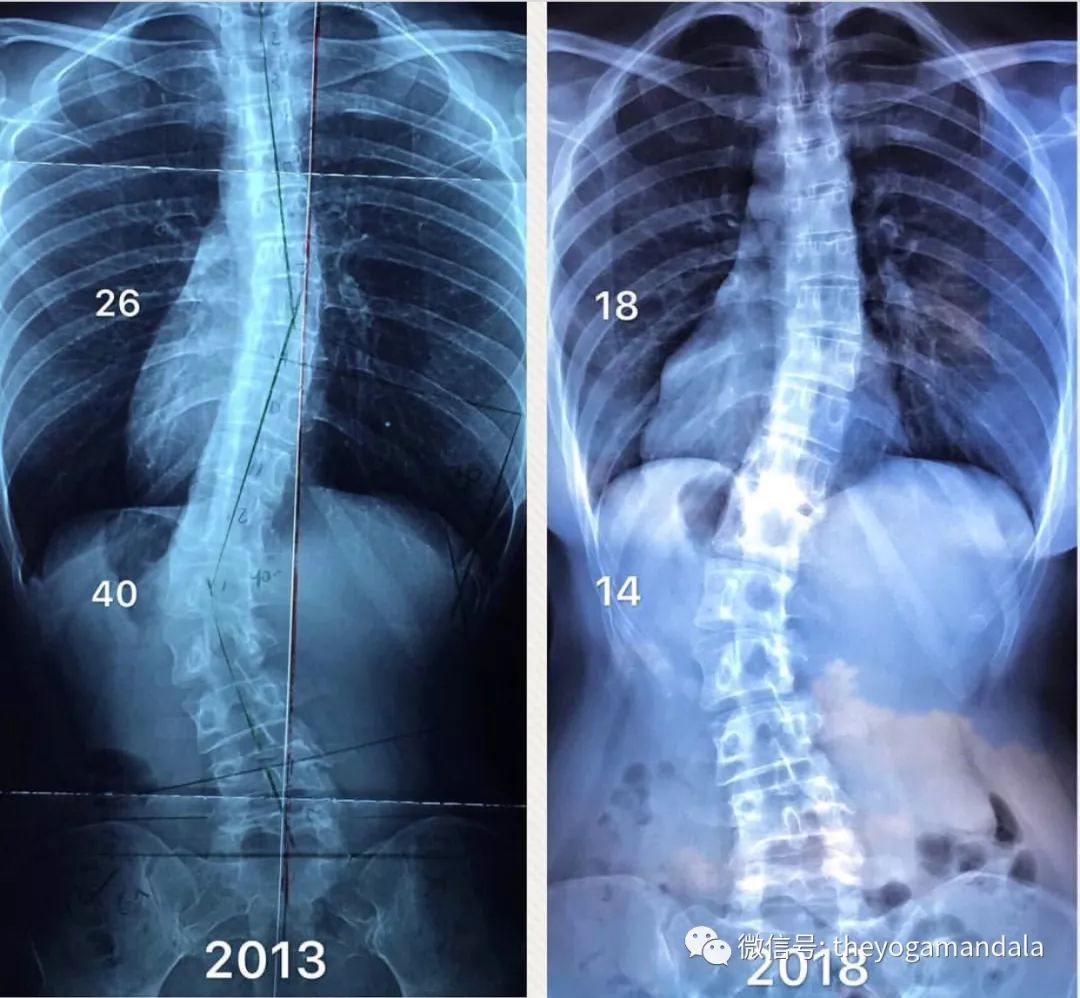

Jessica 出生于新加坡著名健美教练的家庭,她的母亲曾多次代表新加坡参赛并获得荣誉。Jessica 自幼热衷于参加各类体育运动,包括马拉松,障碍赛及泰拳。天生的脊柱侧弯使她决定用热衷的瑜伽来代替手术。Jessica帮助许多脊柱侧弯的学生进行循序渐进的康复训练,脊柱得到明显改善。